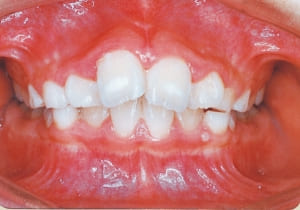

Age at initial visit : 7 y 7 m, male /Protruding upper bite. Open bite. Receding lower jaw. Protruding dual dentition.

1 Initial Visit 2-11-’88

This was a case of significant Protruding upper bite, and early treatment was deemed necessary from a functional perspective.

The Class II condition is pronounced, with a significant overjet of 12.5 mm(3). Although the teeth size are large, crowding is relatively mild. The maxillofacial structure has good depth and a robust bone framework(5). The mandible itself is solid , robust gonial angle, but there is significant anterior-posterior displacement relative to the maxilla(ANB 10.0°). While there is no confirmed history of thumb-sucking or similar habits, the lower lip is already pushing up against the maxillary incisors. The cause of this condition is unknown.